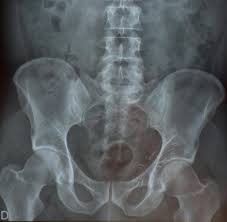

Leistenbruch und Schenkelbruch bei Frauen. Bei Frauen kommt ein Leistenbruch deutlich seltener vor als bei Männern. Bei rund 3 Prozent der Kinder ist eine Leistenhernie angeboren wobei auch hier Jungen die Nase vorn haben.

Männer bilden mit 80 Prozent der Betroffenen die größte Gruppe. Schenkelbrüche führen eher zu Komplikationen als Leistenbrüche. Leichte ziehende Leistenschmerzen auf der betroffenen Seite.

Symptomatisch werden Leistenbrüche häufig erst wenn sich ein größerer Bruchsack gebildet hat. Für einen Leistenbruch sind folgende Symptome bei Mann und Frau kennzeichnend. Eine Schwellung in der Leistengegend die gut zu erkennen und zu ertasten ist.

Zuweilen entwickeln sich Leistenhernien über Monate und Jahre unbemerkt. So wird in der Regel zu einer Operation geraten.